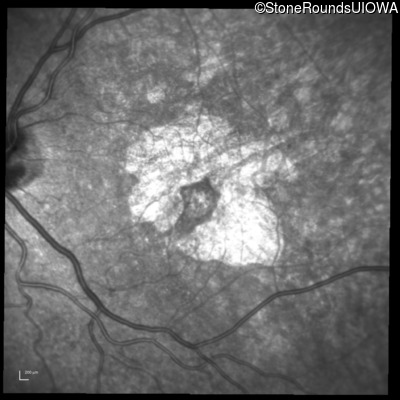

Infrared Fundus Photograph - Right - 20/32 +2

Exemplar